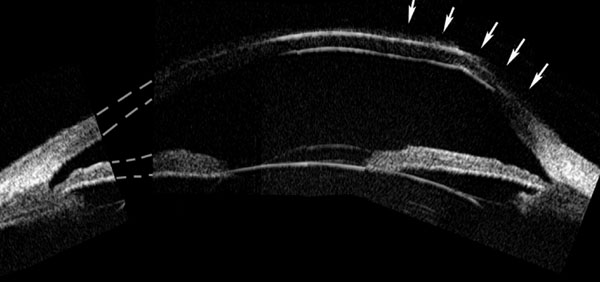

La exploración cuidadosa con BMU permite diferenciar cuatro capas corneales tal como se muestra en la FIG 4.1: Dos líneas altamente ecogénicas que corresponden al epitelio y a la membrana de Bowman, la zona estromal de baja ecogenicidad y una línea de eco brillante debido a la interfase membrana de Descemet-endotelio con el Humor Acuoso. Esta imagen es la referencia que debemos retener para interpretar las alteraciones que se producen en los diferentes procesos patológicos que afectan a la córnea.

FIGURA 4.1: Imagen de BMU de una córnea normal. Dos líneas altamente ecogénicas que corresponden al epitelio y a la capa de Bowman, la zona estromal de baja ecogenicidad y una línea de eco brillante debido a la interfase membrana de Descemet-endotelio con el Humor acuoso. (I.N.G.O.)